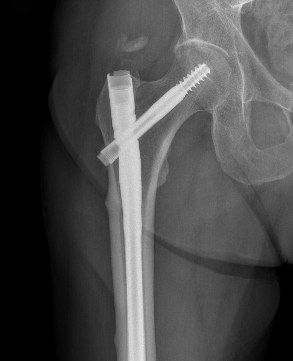

1. Cephalomedullary nail

Nail aptypical 1Nail atypical 2

Femoral stress fractureFemoral Stress Fracture IMN

complete AFFNail AFF